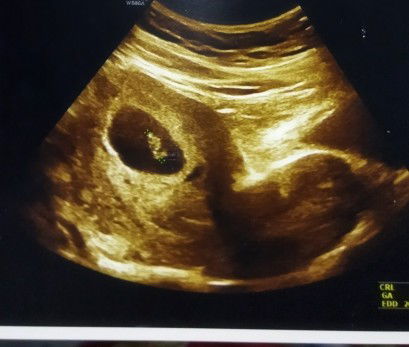

Perdarahan di sekitar kantung janin

Hallo moms2 disini ada yang pernah mengalamin sprt saya ga ya? 2 hr yg lalu usg dokter blg ad perdarahan di sekitar kantung janin & saya ada keluar flek bahkan sampai pendarahan..usia kehamilan saya skrg memasuki 7weeks